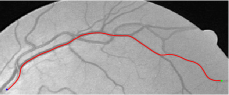

Compare to existing minimal path models. The Riemannian metrics used in [1, 4, 5] are based on the local pointwise information. The curvature-penalized metric [7, 6] and the proposed coherence-penalized metric are able to consider more constraints, i.e., the rigidity for [7, 6] and feature coherence for our metric. These constraints are beneficial to the respective geodesics to reduce the risk of short branches combination problem. Compared to the curvature-penalized metric, our method can be more flexible since the feature map can be produced dependently on the task. In retinal imaging, veins and arteries are distinguishable in terms of gray levels or vesselness values, satisfying the formulation of the proposed model. Especially for vessels with strong tortuosity, the curvature-penalized metric, which favours a smooth curve, fails to catch the expected vessels as shown in the left column of Fig. 2. From the right column of Fig. 2, one can see that our model can obtain a good result.

Validation. We validate our minimal path model on respective 54 and 30 patches obtained from the DRIVE [14, 15] and the IOSTAR [16] datasets with AV groundtruth. Each artery involved in these parches locates near a vein or crossing it at least once. Our goal is to extract the artery between two given points. In order to get the quantitative evaluation, we first convert each continuous spatial path to an 4-connected digital path which is considered as a pixel collection. We denote by the collection of digital path pixels inside the artery groundtruth map . Thus, a measure can be simply defined as , where and mean the respective number of elements involved in and . We compare our model to four existing minimal path models: the isotropic Riemannian (IR) model [1], the anisotropic radius-lifted Riemannian (ArR) model [4], the isotropic orientation-lifted Riemannian (IoR) model [5] and the curvature-penalized (CuP) model [7]. The construction of these metrics are based on the OOF outputs [12]. Note that a centerline-based potential is chosen so that we remove the radius dimension of [5] to reduce computation complexity. The results in terms of the score are presented in Table 1, including the average (Avg.), maximum (Max.), minimum (Min.) and standard deviation (Std.) values. In both DRIVE and IOSTAR datasets, our method can achieve the best performances thanks to the coherence penalization. Note that in Table 1, we evaluate our method by using the refined paths instead of using the original coherence-penalized minimal paths. For comparisons in visualization, we show the minimal paths from the ArR metric , the CuP metric and the proposed coherence-penalized metric on three retinal patches as shown in Fig. 3. The targeted artery vessels which cross veins at least once are labeled by red color in column 1. The paths shown in column 4 from the proposed metric are results after refinement. One can claim that our method indeed can catch expected arteries while other metrics fall into the traps of short branches combination.